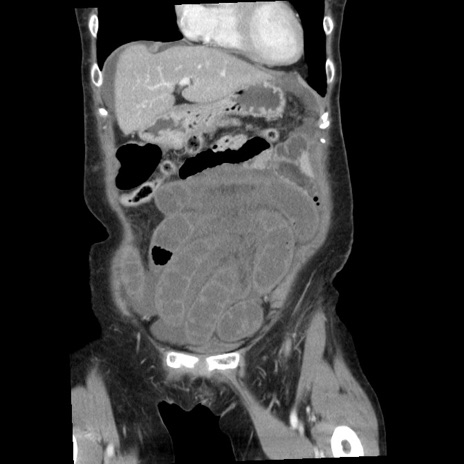

症例1(冠状断像)

【症例】80歳代女性

【主訴】腹痛

【現病歴】8時間前から腹痛あり来院。

【既往歴】糖尿病、脂質異常症、子宮体癌にて子宮全摘術

【身体所見】意識清明・会話良好だが腹痛で苦悶様、全腹部にわたって反跳痛と圧痛あり

【データ】WBC 13600、CRP 0.14、LDH 224、CK 90